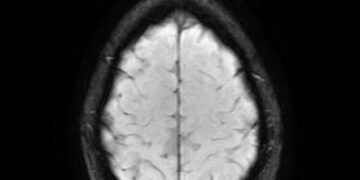

Read moreScience Reveals How To Avoid Dementia A new study from Sweden suggests that improving cardiorespiratory fitness (CRF) may help reduce...

Read moreThe Dangerous Combination Impacting Brain Health Joint pain and depression in older adults may not only affect physical well-being but...